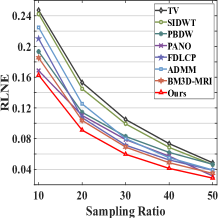

First, we test on 25 T1-weighted MRI data using three different undersampling patterns with a fixed 10% sampling rate. Fig. 3 shows the quantitative results (PSNR). Our method performances best for all three cases and has stronger stability compared with the second best method on variance. As for the effect of sampling ratios variation, we use radial mask under 10%, 30% and 50% sampling rates with evaluation of RLNE and MSE. Fig. 4 shows that our method has the lowest reconstruction error for all sampling rates. For more intuitive comparison, we illustrate the reconstruction error in term of pixels in Fig. 5. We also offer the qualitative comparison in Fig. 6. Visualized results demonstrate our method has better performance in both artifacts removing and details restoration. Time consuming is also considered. We compare our method with others on the 25 T1-weighted data using Radial mask with 10% and 50% sampling rate. Notice that ADMM-Net and ours are tested on GPU for the incorporation of deep architecture. Tab. 1 shows that our method provides an efficient reconstruction process and comes to the fastest method among the state-of-the-art competitors.